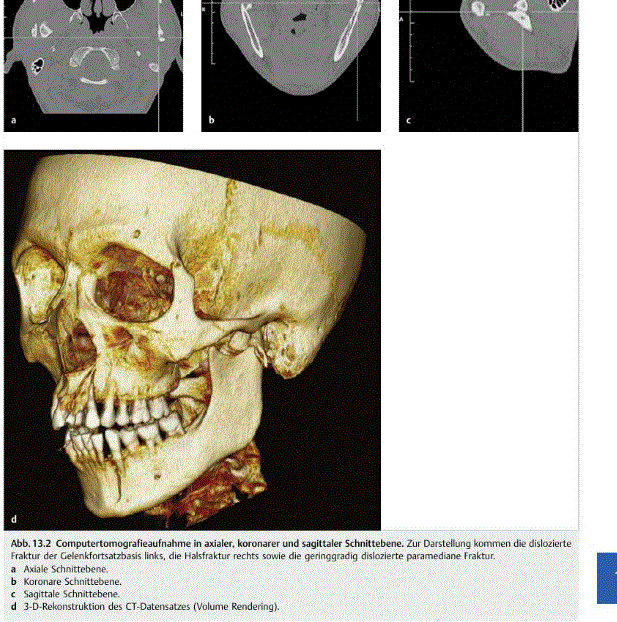

Welche Aufnahme ist es ?

Welche Ebene ?

Diagnose ?